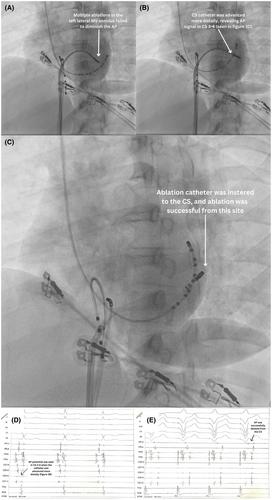

心外膜旁道不常见部位:冠状窦、心房附件、主动脉尖。

Uncommon sites of epicardial accessory pathways: coronary sinus, atrial appendage, aortic cusps.